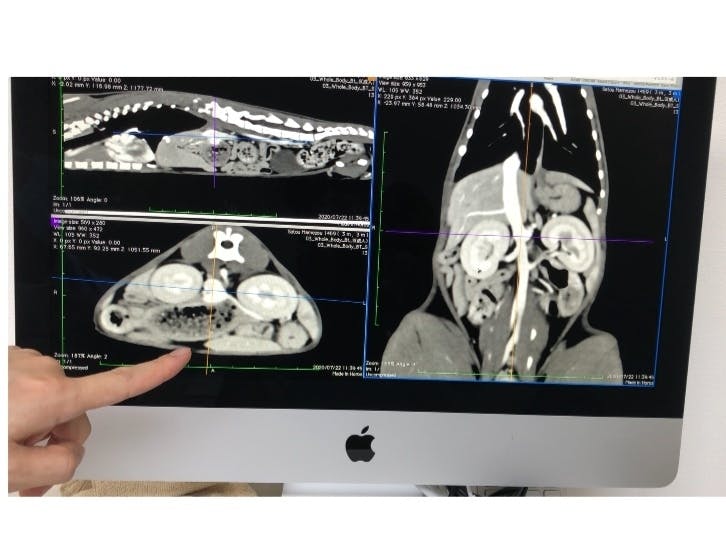

急いで病院に行き検査をしたところ、腹水が微量に溜まっていて、アンモニアの数値が600超えという考えられない程高いもので、病院の診断は【門脈シャント】という病気でした。

【門脈シャント】とは、本来肝臓に入るべき胃腸からの血液が「シャント」と呼ばれる異常な血管があることにより、毒素が全身に巡ってしまう病気です。

それでも食欲は旺盛で、毎日短時間ですがはしゃいでいる姿はとても可愛くて、手術をできる状態にもっていけるように預かりBABAさんが毎日の投薬に励み、ようやく先日CTスキャンによる検査を受けてきました。

画像診断の結果は、門脈シャントと確定したものの、門脈が異様に細い為かなり難易度が高い手術だということで、1度の手術では対応出来ず、最低でも2回、もしくは3回に分けて手術をしなければならず、1回目の手術代の目安は約20万円、2回目の手術と術前のCT検査で20万円、3回目は15万円ととても高額な目安になると言われました。